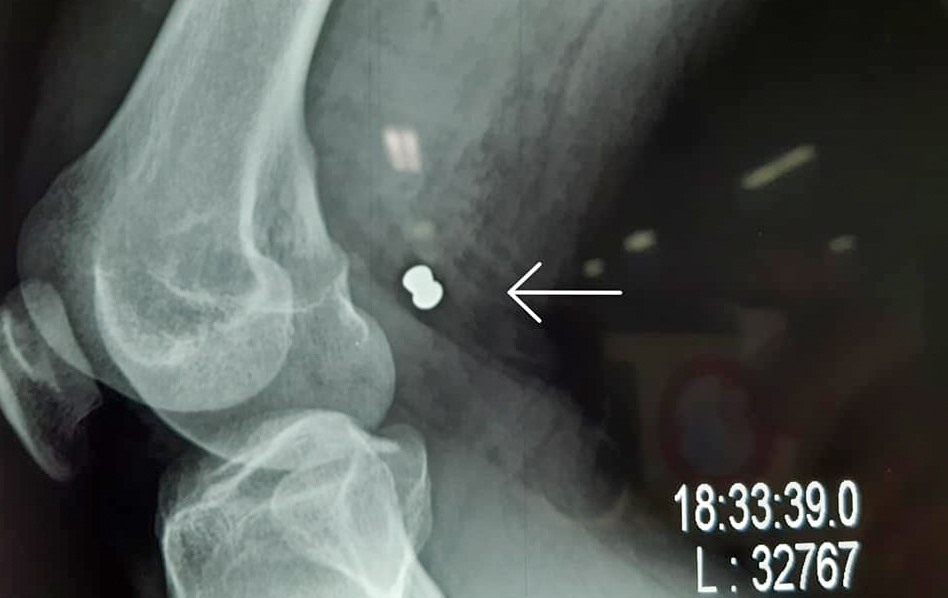

Viên đạn găm vào đùi phải của anh H. (Ảnh: Bệnh viện cung cấp)

Sau khi siêu âm, chụp X-quang, bác sĩ xác định trong đùi phải anh H. có một viên đạn, khả năng làm tổn thương các mạch máu.